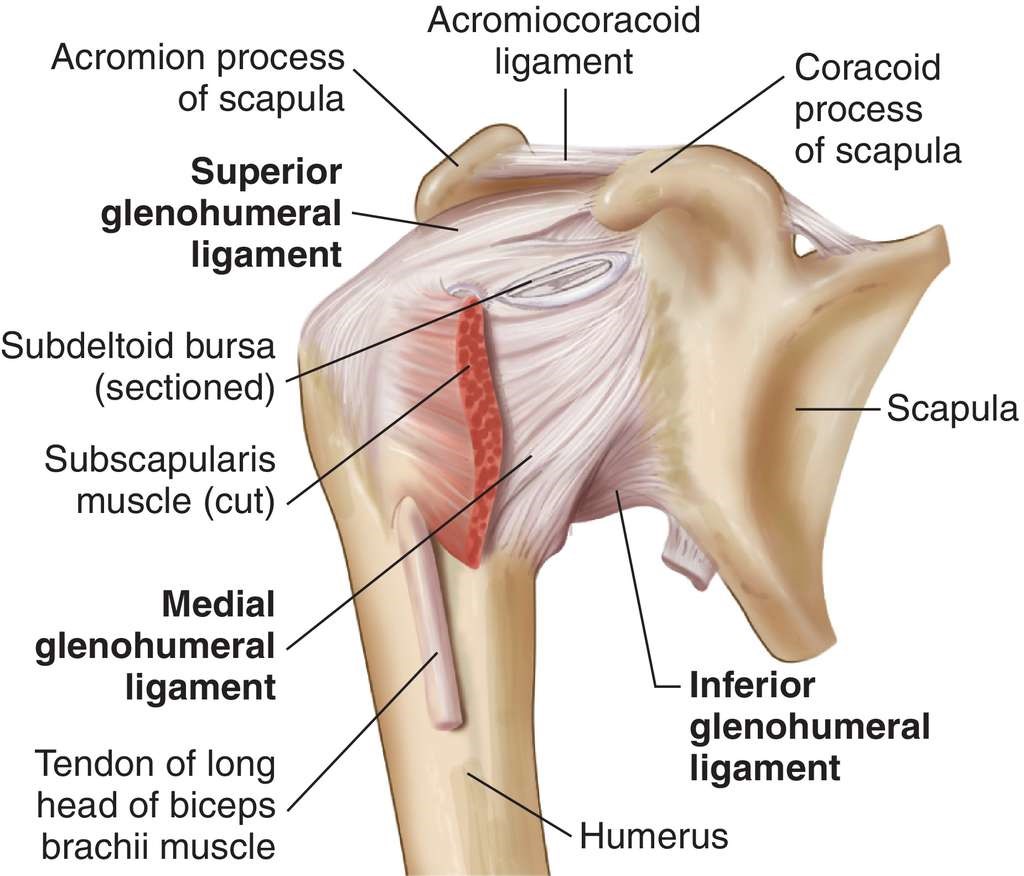

Glenohumeral ligament: анатомия и функции плечевого сустава